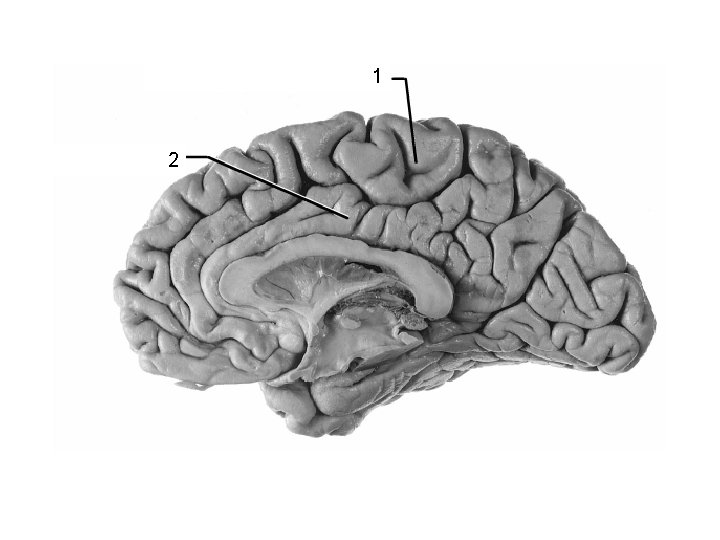

1 Thalamus 2 3 4

1 Thalamus 2 3 Lentiform Nucleus

1 2 Putamen 3 (lentiform nucleus)

ant. limb, Int. capsule (frontal eye field fibers) 1 head of caudate nucleus 2 frontal horn, lateral ventricle 3 optic chiasm 4 putamen ICA

Post. limb, int. capsule: corticospinal + corticopontine 2 + thalamocortical fibers Body 3 of lateral ventricle thalamus 4 descending cortical 1 fibers in crus cerebri of midbrain 5 Ventricle III Lentiform nucleus 6 putamen is visible) (only